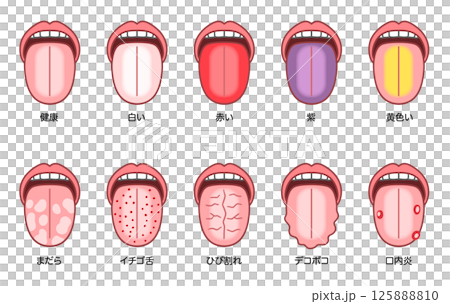

体調が丸わかり"危険な舌"の状態はこれだ 舌は「健康のバロメーター」週刊女性PRIME東洋経済オンライン。

白い、ガタガタ、ひび割れ 。“舌”でわかる体調不良のサインとは?田中友也さん 季節の養生法からだにいいこと。

舌のサイン 院長ブログ八尾市のオカモト鍼灸整骨院。

舌診~毎日鏡の前で健康チェックをしたくなる舌の状態を解説 祥泉針灸整骨院。

石豆。舌は健康のバロメーター三越前駅小伝馬町歯科 ハルデンタルオフィス。

石豆。舌は健康のバロメーター三越前駅小伝馬町歯科 ハルデンタルオフィス。